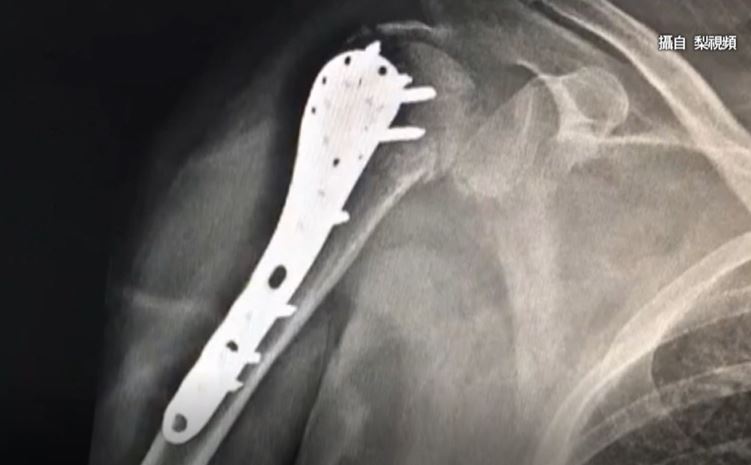

▼(圖/翻攝自 梨視頻)

浙江醫院副院長宋柏杉:「所以說雖然她年齡不大,才五十多歲,但是她這個骨質酥鬆,已經相當於比七十多歲的老年人,還要嚴重。」

浙江醫院副院長宋柏杉:「這個人原本就患有多年的,類風濕關節炎,一直在服用一個皮質激素,長期服用這個藥,有一個嚴重的副作用,就會引起骨質酥鬆。」

由於張姓婦人年紀不大,但考慮到婦人還算年輕,骨骼還有比較強的生長能力,因此改進行復位內固定術,將鋼板放進婦人肩膀,所幸手術順利已經回家休養,但這位受驚嚇的老公,應該暫時不敢再碰太太了。